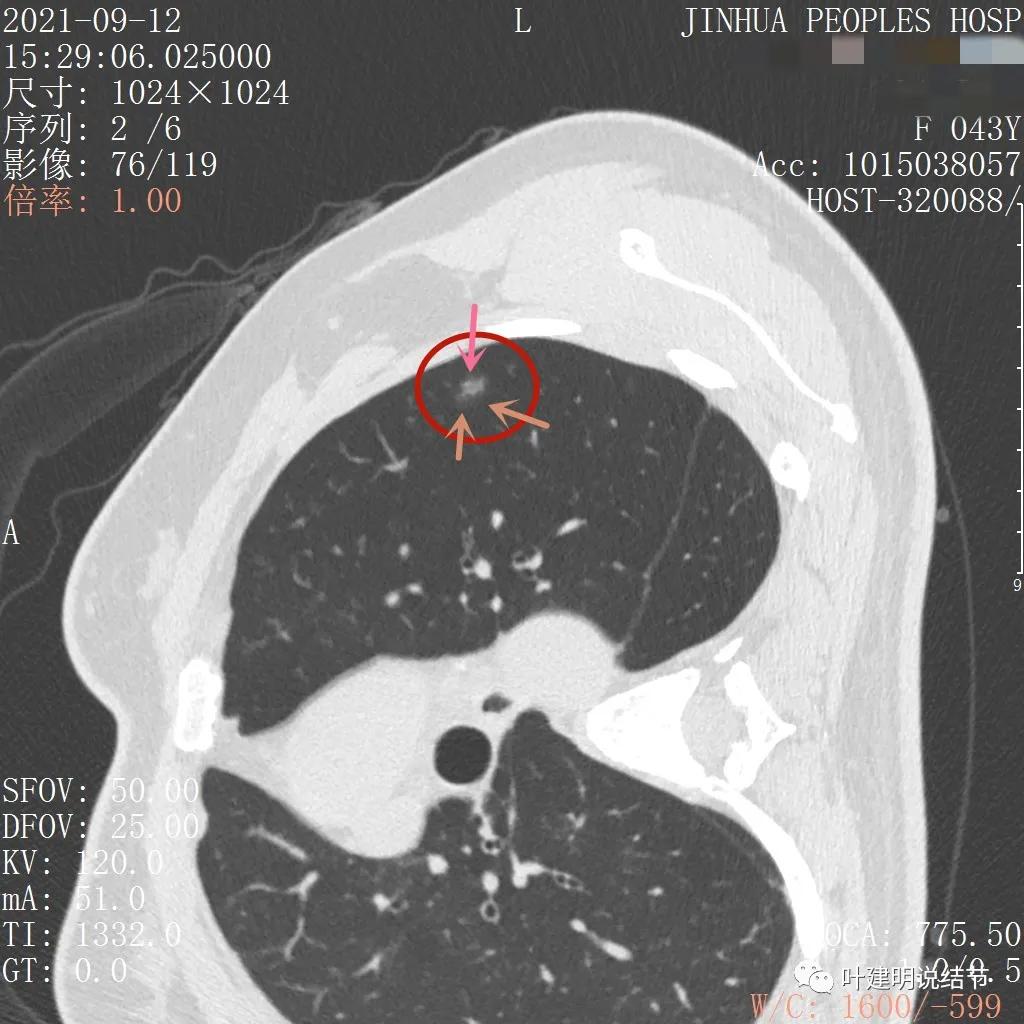

上图示瘤肺边界处显模糊(砖色箭头),病灶内部仍是有偏高密度的点状成分

上图层面也显示病灶边缘欠清,有些模糊,虽总体轮廓还是比较清晰

从以上靶扫描图像上看,给人的印象是肿瘤范畴的结节,是混合磨玻璃结节,但磨玻璃部分的密度偏低,有的边缘显模糊,中间有点状高密度,也有微小血管进入,应该至少微浸润性腺癌可能性大。持续存在已经2月余,位置又还靠边上的,可考虑手术切除。下面再来瞧瞧后处理重建的图像: